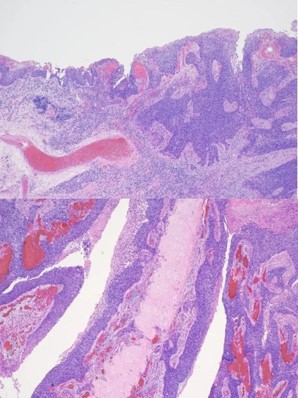

The patient was seen in an outpatient setting for a two week follow-up and discussion of final pathology results. These showed two masses: ameloblastoma with the invasion of the hard palate, posterior maxilla, and maxillary sinus (Figure 5) as well as a SCC with the cartilaginous and bony invasion of the nasal septum and nasal bone (Figure 6). During this clinic visit, he reported some discharge from one of the incisions and flap edema. He was otherwise doing well, with significant improvements in dysphagia and nasal obstruction. The flap adhered well to native tissue and appeared healthy. The infection cleared up over the next two weeks on a course of antibiotics, and the patient’s nasogastric tube was removed within the following three weeks.

We report a case of extensive nasal bone, hard palate, and sinus invasion from squamous cell carcinoma, which muddied the identification of an ameloblastoma. Simultaneous occurrences of ameloblastomas and SCC are rare, and it is difficult to appreciate both entities during initial examination. The ameloblastoma was present along the left maxillary sinus, posterior maxilla, and hard palate. Where moderately differentiated keratinizing squamous cell carcinoma was seen along the nasal bone and septal cartilage. In this case, metastatic disease was not found, and the margins were negative. The pathological staging was pT3N0M0 and pT4N0M0 for the ameloblastoma and squamous cell carcinoma, respectively. He was referred to radiation oncology and recommended to proceed with radiation therapy, but the patient opted not to pursue it. Previous case reports discuss the radiosensitivity of squamous cell carcinoma and the uncertainness of the role of radiation therapy in ameloblastomas [5,6].